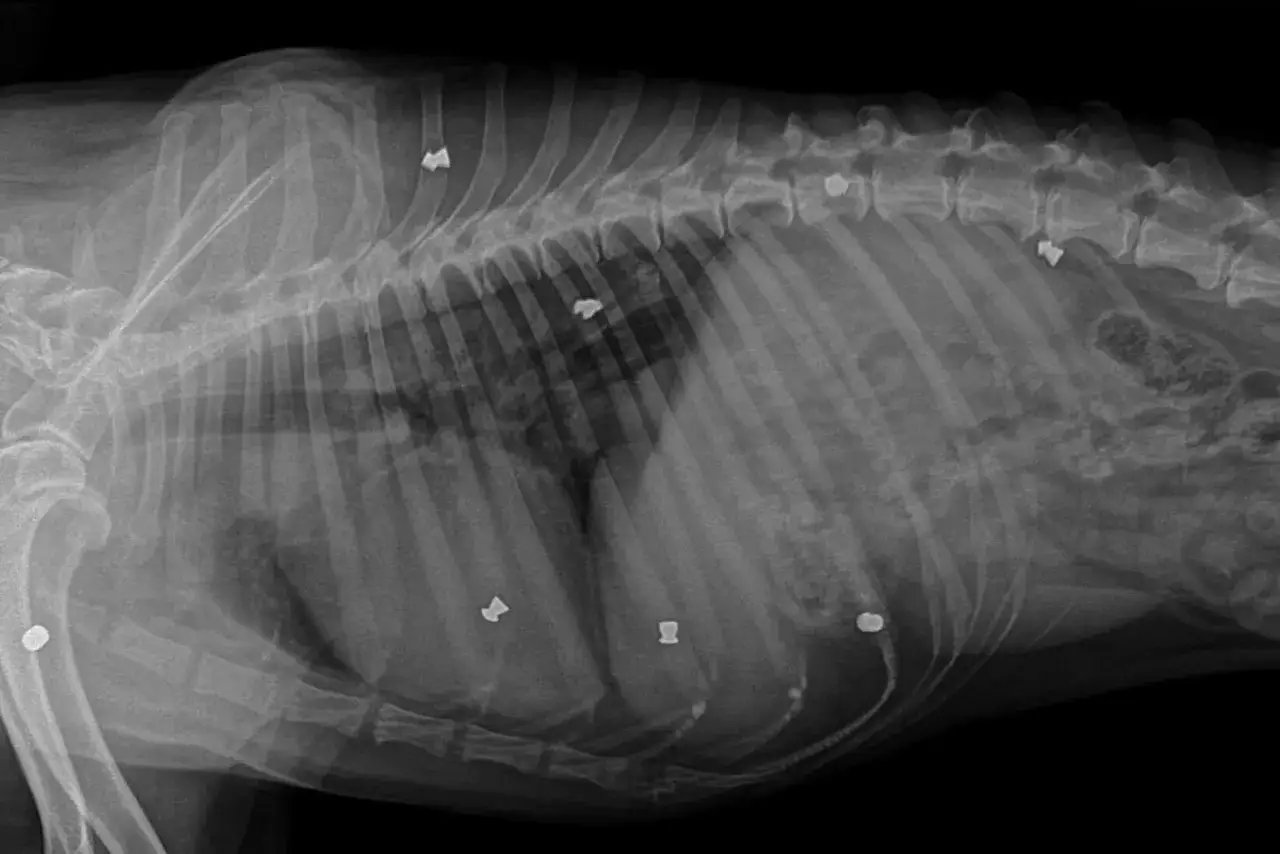

1. Liczba projekcji: Badanie klatki piersiowej psa zazwyczaj wymaga wykonania minimum dwóch projekcji bocznej (pies leży na boku) oraz grzbietowo-brzusznej (pies leży na plecach lub na brzuchu). Taki zestaw zdjęć jest niezbędny do pełnej oceny wszystkich struktur i pozwala lekarzowi na dokładną diagnostykę. Każda dodatkowa projekcja to oczywiście kolejny koszt, który jest doliczany do rachunku.

Badanie RTG klatki piersiowej jest potężnym narzędziem diagnostycznym w rękach weterynarza. Zleca się je w wielu sytuacjach, gdy istnieje podejrzenie poważnych problemów zdrowotnych u psa. Pozwala ono na wizualizację narządów wewnętrznych i struktur kostnych, co jest nieocenione w procesie diagnozy.

- Urazy: W przypadku podejrzenia urazu klatki piersiowej, na przykład po wypadku komunikacyjnym lub upadku, RTG pozwala ocenić ewentualne złamania żeber, obrażenia płuc czy serca.